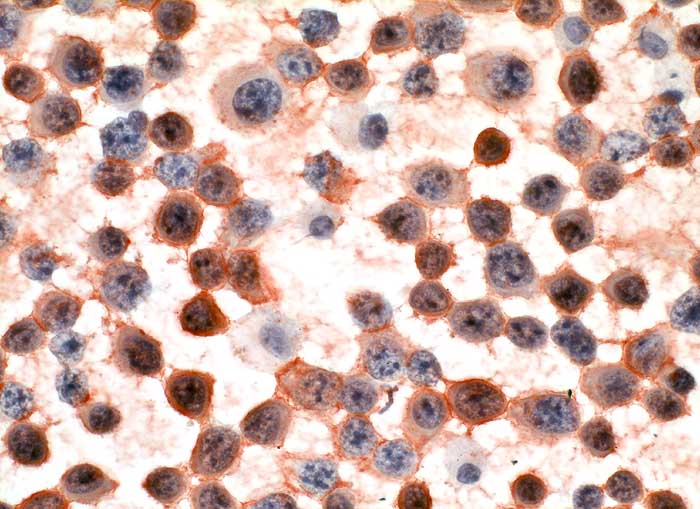

CD138

- Anfärbung:

- Zellmembran

- Plasmazellen sind positiv.

- Neoplastische Plasmazellen reagieren positiv.

- Diagnose des multiplen Myeloms. Identifikation von Plasmazellen.